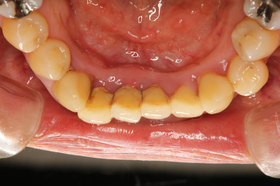

下の写真は、基本治療終了時の写真です。

全顎的に炎症は改善し、歯肉は引き締まり、きれいなピンク色になってきています。

上顎前歯4本には連結された暫間クラウン(仮歯)が装着されており、歯の動揺もなく、審美性も改善しています。

歯周病の原因やプラークリテンションファクターの除去を行うことで、本来持っている生体の治癒力を高め、歯周組織もここまで良好になります。